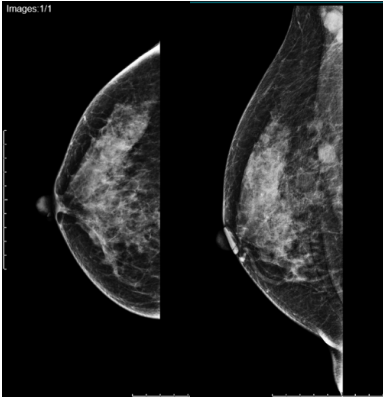

2021年6月20日乳房钼靶:右乳上方深部见直径12mm结节,边界欠清,右侧腋下见肿大淋巴结影。

结论:右乳上方结节,右腋下淋巴结肿大,BI-RADS 6

图3.右乳钼靶